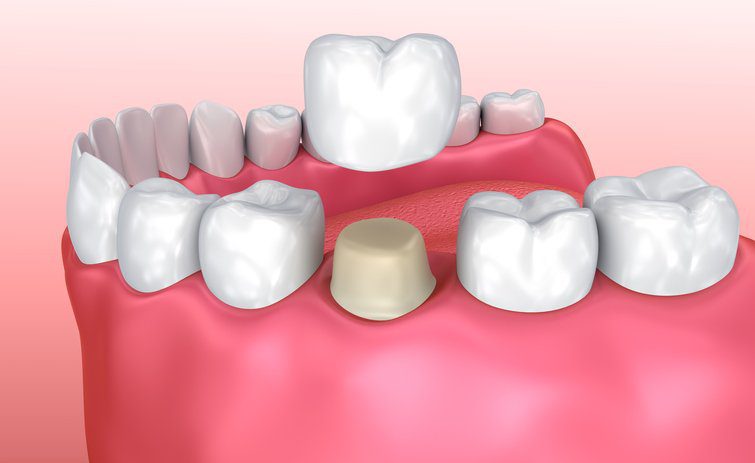

تيجان الأسنان هي أغطية على شكل قبعات و توضع التيجان أعلى سنك لاستعادة الأجزاء المفقودة أو التالفة و باستخدام التاج لتغطية المناطق الحساسة من أسنانك يمكنك حماية هيكلها وحمايتها بشكل أكبر من الأذى.

تاج الأسنان عبارة عن سن زائف مجوف تم تصميمه ليلائم الأسنان الموجودة بعد قصها وتشكيلها , يغطي التاج السن بالكامل ويغطيه ويغطيه حتى خط اللثة ويعيد شكل ولون ووظيفة السن.